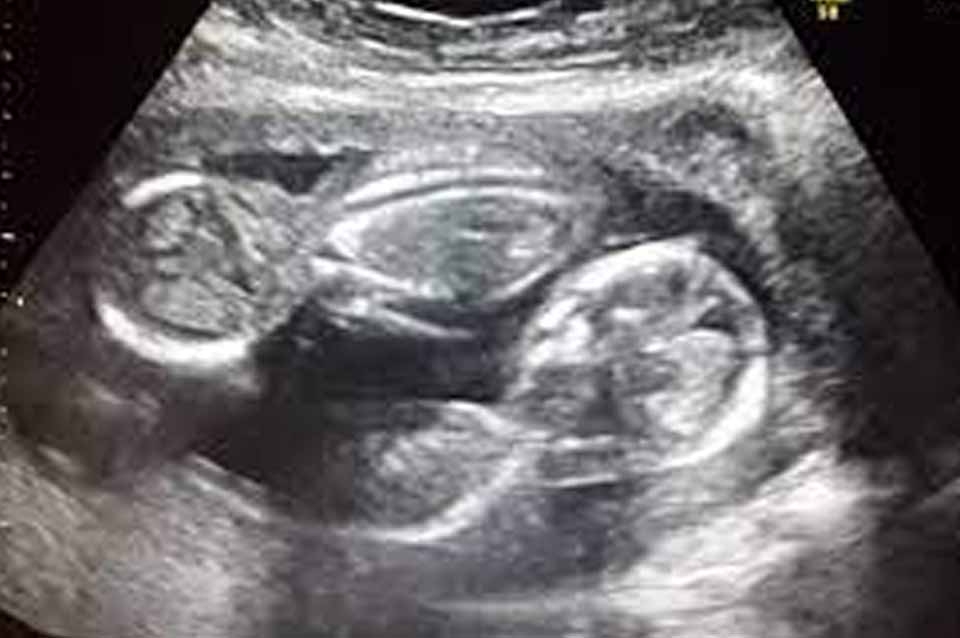

Una mujer dio a luz a mellizos de padres diferentes

Un médico brasileño reveló que una joven de 19 años que él había atendido dio a luz a mellizos de padres diferentes. Los niños ahora tienen 16 meses y son cuidados por la madre y uno de los dos hombres.

Para el médico Jorge Franco se trata de un raro caso de “superfecundación heteropaternal”.

“Es posible que suceda cuando dos óvulos de la misma madre son fertilizados por hombres diferentes. Los bebés comparten el material genético de la madre, pero crecen en diferentes placentas”, dijo Franco en conversación con Globo.